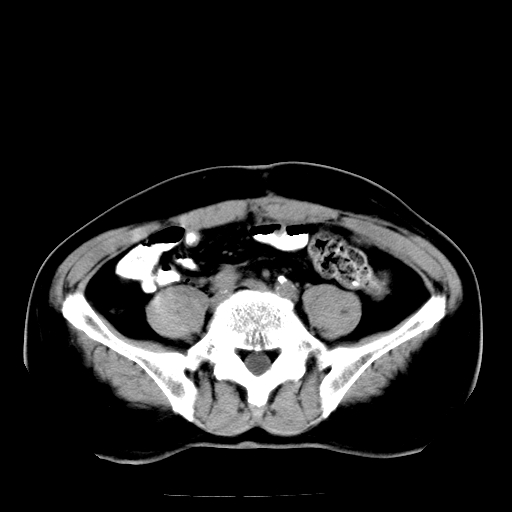

男,66岁,直肠癌术后一个月,化疗前ct检查。

直肠癌造瘘术后改变,周围淋巴结转移

前列腺肥大

直肠癌造瘘术后改变,盆腔多发淋巴结转移

直肠癌造瘘术后改变,直肠周围软组织增厚,盆腔多发淋巴结转移。前列腺肥大。